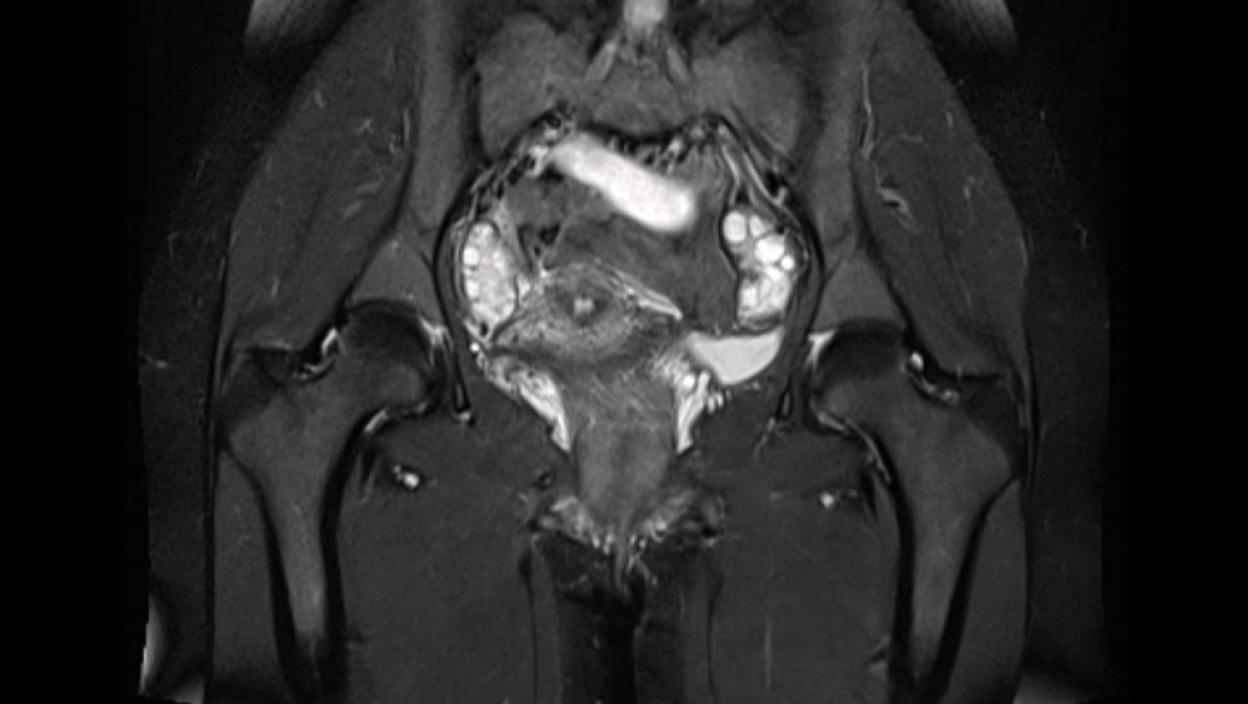

Na društvenim mrežama incident je izazvao burne reakcije, a jedan korisnik platforme X podelio je fotografiju uz upozorenje da se nikada ne ulazi na pregled magnetnom rezonancom sa metalnim predmetima u telu.

Prema dostupnim informacijama, 22-godišnja pacijentkinja verovala je da je analni čep koji je nosila napravljen isključivo od silikona. Međutim, ispostavilo se da je u sebi sadržao metalne delove, što je tokom MRI pregleda dovelo do izuzetno opasne situacije.

Pod dejstvom snažnih magnetnih talasa, predmet je povučen dublje kroz telo, izazivajući teške unutrašnje povrede i dospevši sve do grudnog koša.